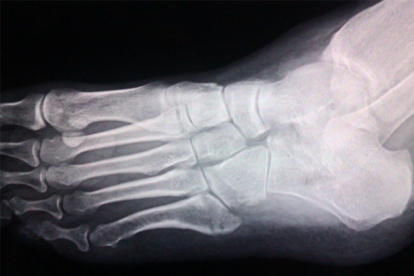

应力性骨折常见于运动员或突然增加运动量的人群,足部骨骼因重复应力出现微小裂纹,疼痛随活动量增加而加剧。初期需制动4-6周,严重者需石膏固定,可遵医嘱使用骨肽注射液或鹿瓜多肽注射液促进愈合。恢复期应逐步增加康复训练,避免过早负重导致骨折线扩展。